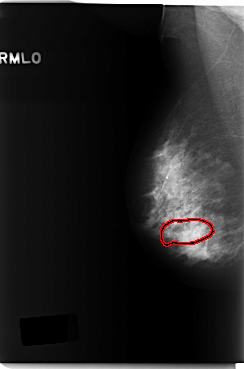

FILE: C_0232_1.RIGHT_MLO.OVERLAY

TOTAL_ABNORMALITIES 1

ABNORMALITY 1

LESION_TYPE CALCIFICATION TYPE FINE_LINEAR_BRANCHING DISTRIBUTION SEGMENTAL

ASSESSMENT 5

SUBTLETY 4

PATHOLOGY MALIGNANT

TOTAL_OUTLINES 1

BOUNDARY

C_0232_1.RIGHT_MLO